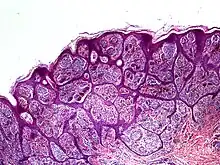

Histology

High-powered imaging tools may identify one or more traits that prove a lesion is a malignant melanoma, rather than a benign nevus:[2]

- Slight pleomorphism of individual cells

- Nuclear atypia with prominent nucleoli

- High rates of mitotic activity (however, some benign nevi also exhibit this trait)[5]

- Penetration through lower tissue layers

In some cases, it may be difficult to identify these features even with a dermatoscope. This is because some nevoid melanomas preserve normal layers of epidermis above them. Excision and biopsy of the suspected lesion can identify nesting, atypical growth patterns, and other hallmarks of malignant growth.[2] In particular, patterns of confluence among melanocytes, parallel arrays of nested cells (parallel theque pattern), and a lack of connective tissue in the lesion should strongly increase suspicion of a malignant nevoid melanoma.[3]